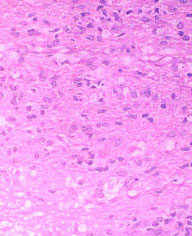

Cases